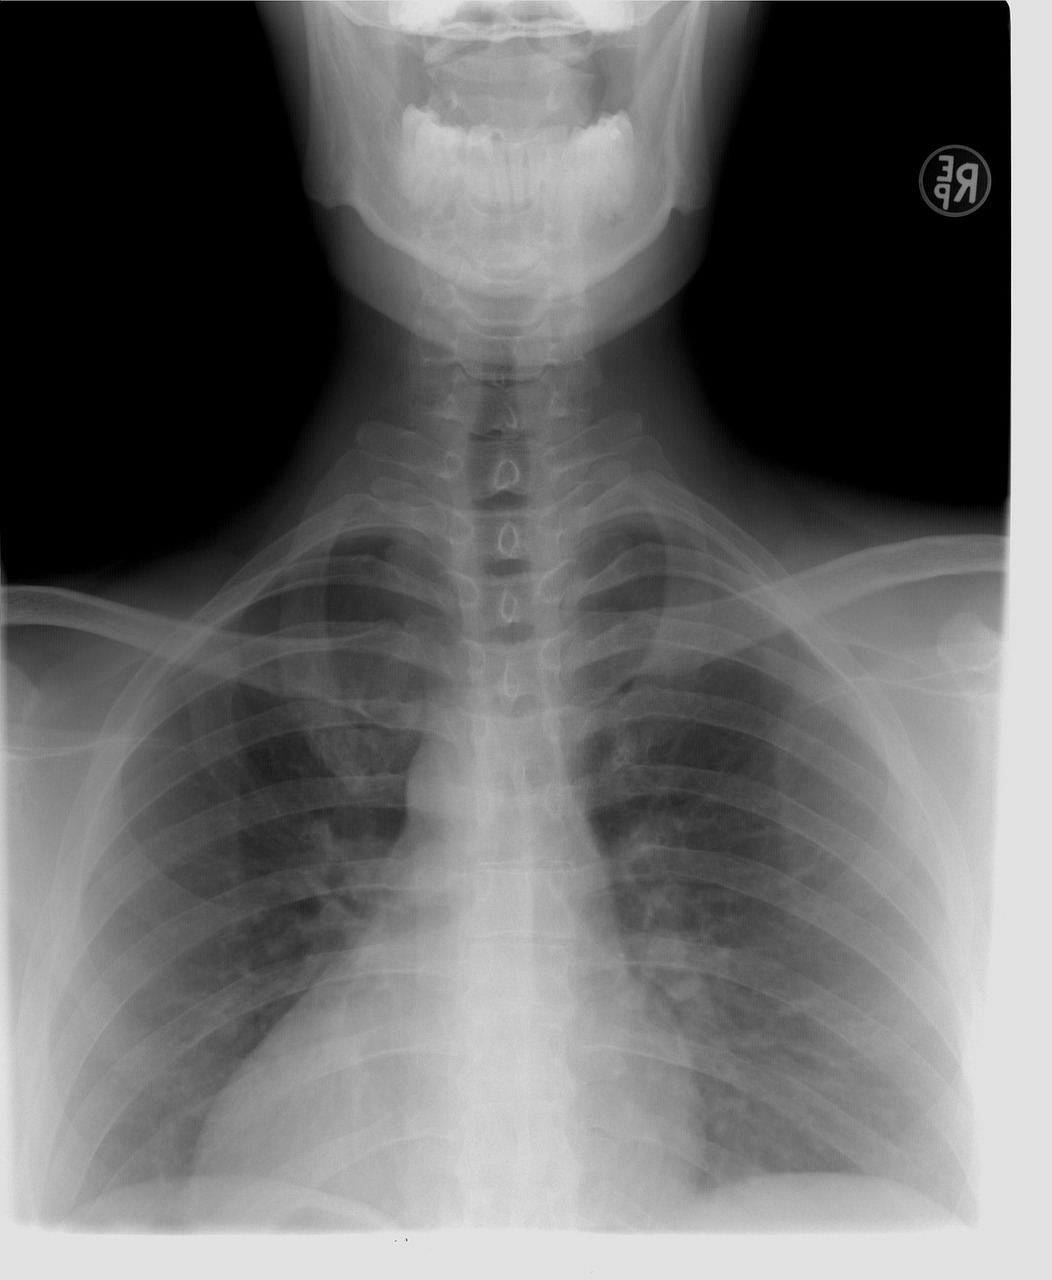

잠복결핵은 결핵균이 몸속에 있지만, 면역체계가 균을 억제하고 있어 증상이 나타나지 않는 상태를 말해요. 활동성 결핵과 달리 전염성은 없지만, 면역력이 약해지면 언제든 활동성 결핵으로 발전할 수 있어 시한폭탄이라고 불리기도 합니다.

결핵은 한국인 사망 원인 중 꾸준히 상위권을 차지할 만큼 심각한 질병입니다. 특히 잠복결핵은 스스로 인지하기 어렵기 때문에 검사를 통해 미리 발견하고 치료하는 것이 중요해요.